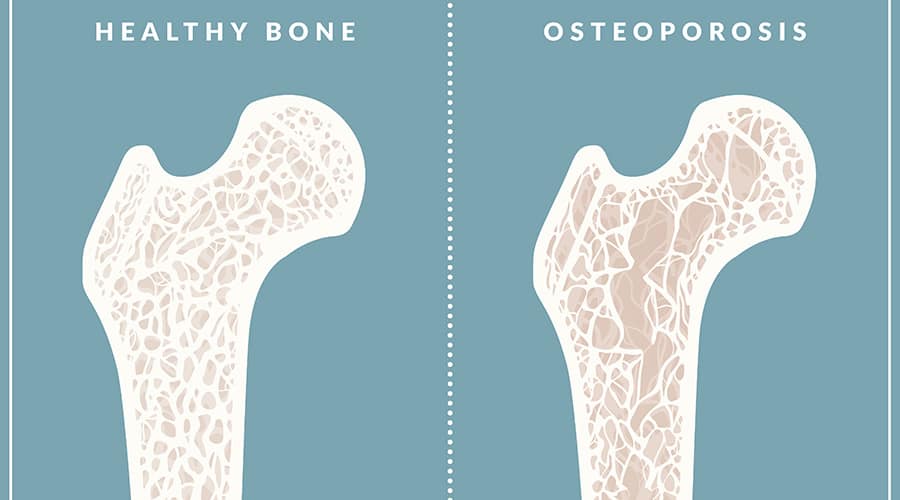

Osteopenia and Osteoporosis: Should Women Worry?

Osteopenia and Osteoporosis are two conditions related to bone loss that can develop as a result of poor…